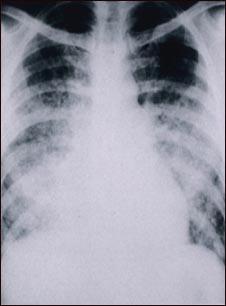

Pulmonía aguda por varicela - Rayos X de tórax

Esta radiografía muestra nubosidad en los pulmones debido a una neumonía aguda posterior a varicela. La neumonía rara vez se presenta como complicación de la varicela en los niños, pero sí ocurre en una quinta parte de los adultos.